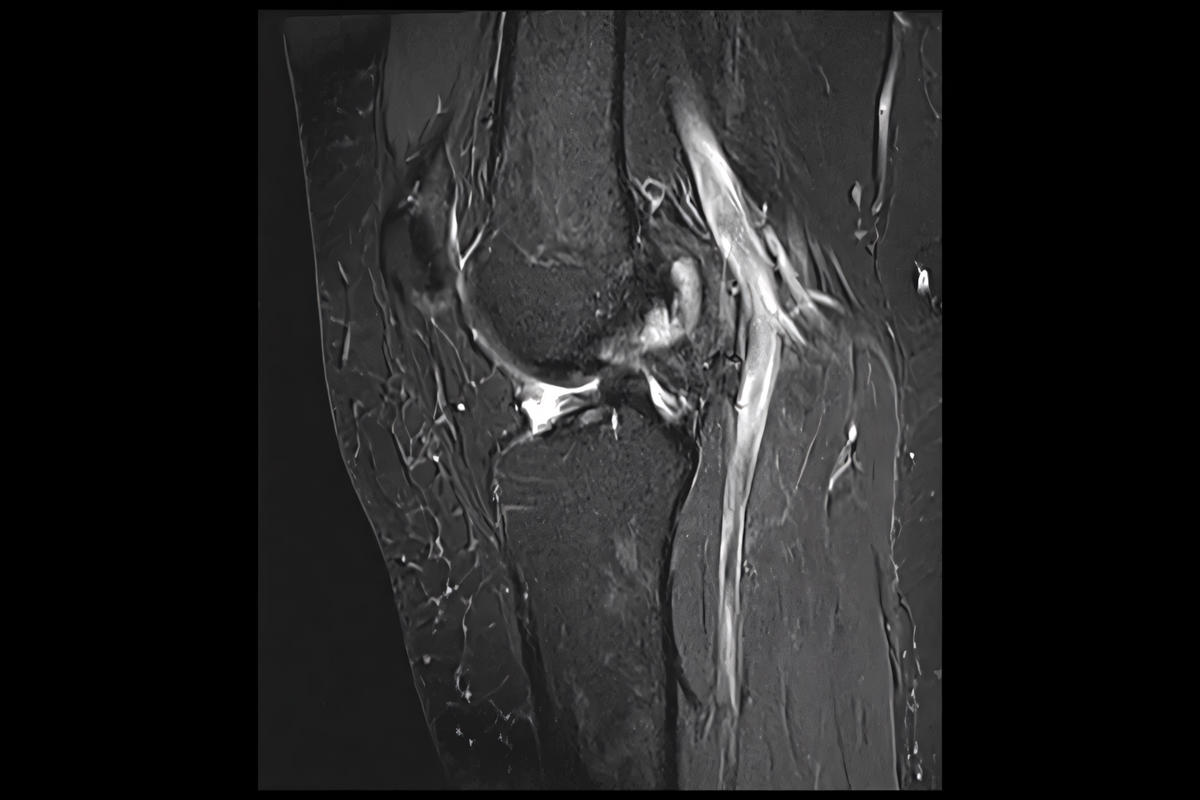

Απεικονιστικός έλεγχος

Ακτινογραφίες για αποκλεισμό οστικών κακώσεων

Μαγνητική τομογραφία (MRI), που επιβεβαιώνει τη ρήξη πρόσθιου χιαστού και αναδεικνύει συνοδές βλάβες σε μηνίσκους, χόνδρο ή πλάγιους συνδέσμους

Η MRI αποτελεί την εξέταση εκλογής για την τεκμηρίωση της βλάβης.